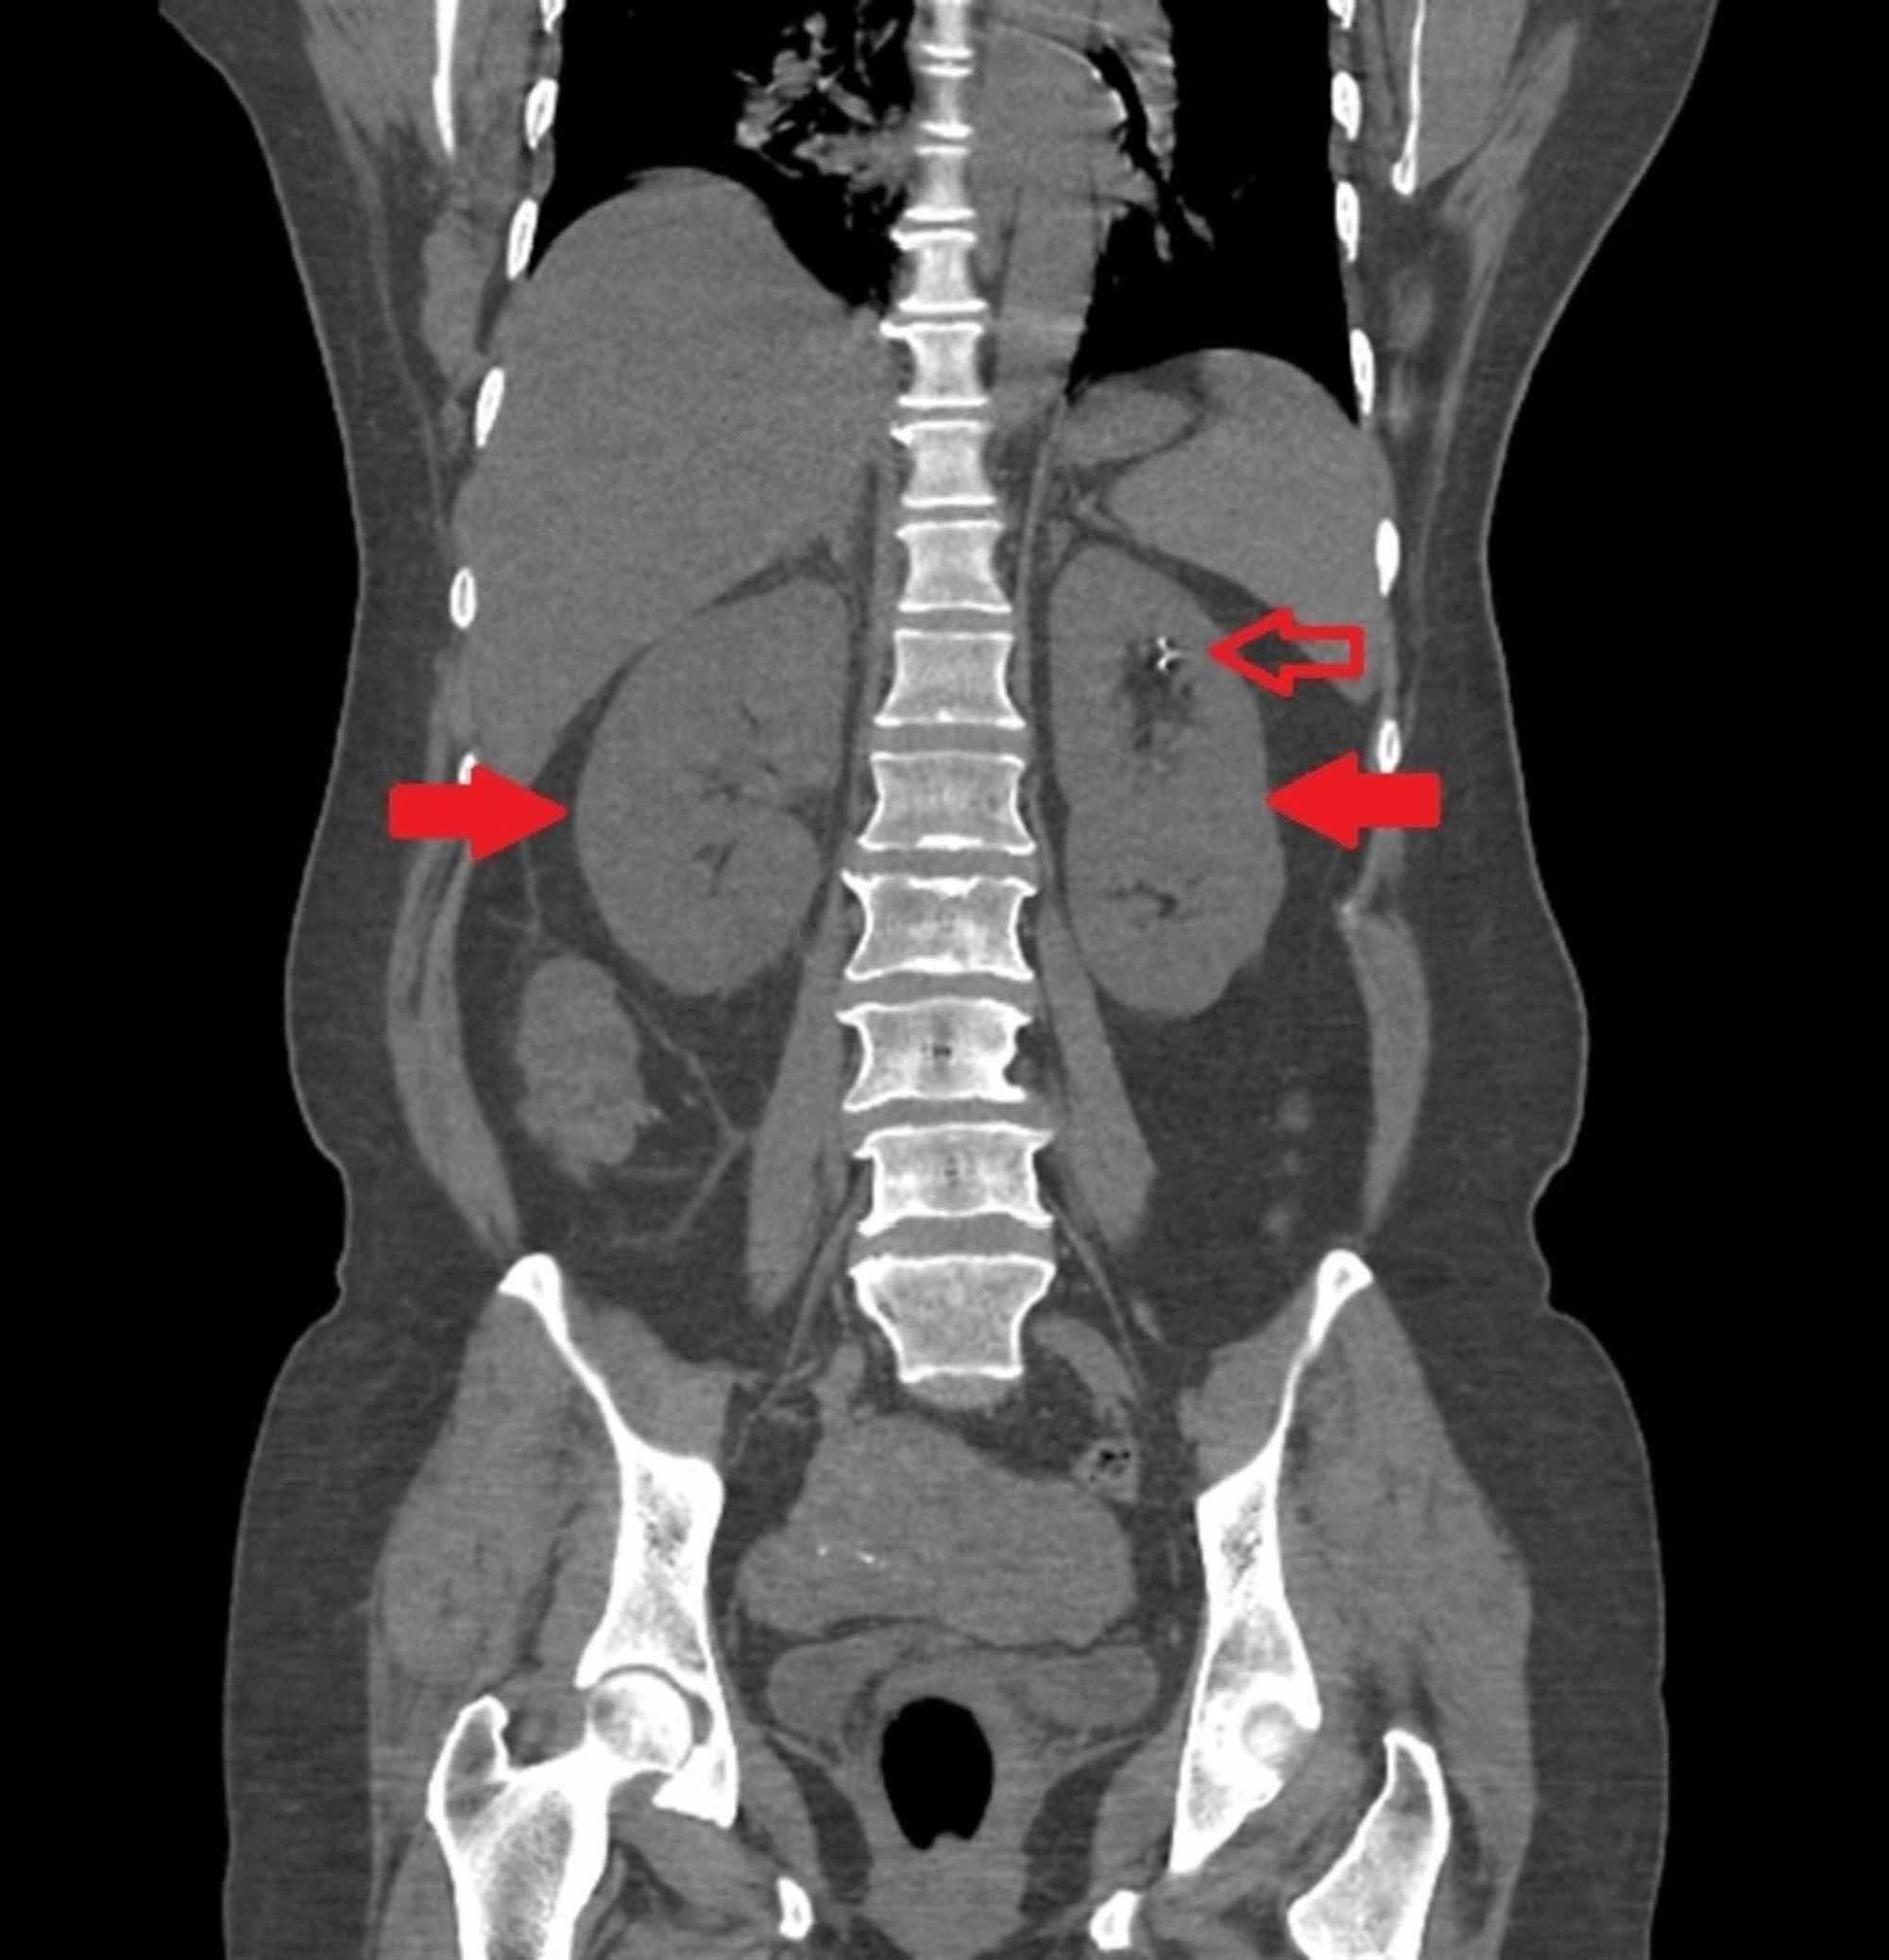

Bilateral Cystic Kidneys With Non Obstructive Calculi Seen On Cect